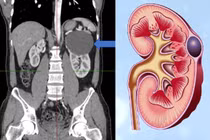

Dị dạng động tĩnh mạch thận hiếm gặp chiếm 0,04% dân số, giai đoạn đầu khó phát hiện qua siêu âm nên bệnh thường chẩn đoán muộn, phải phẫu thuật cắt thận bán phần hoặc cắt thận toàn bộ.

(khoahocdoisong.vn) - Bằng sự chẩn đoán chính xác, phối hợp nhanh và cấp cứu kịp thời, các thầy thuốc của Bệnh viện Bạch Mai đã cứu sống được cả hai mẹ con sản phụ bị vỡ dị dạng động mạch thận.